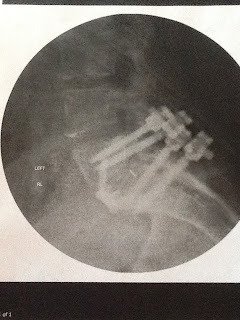

I got pics to share. They are not the best - but it will give you an idea of what I now have.

it is the vertebrae just above the tailbone. Doc said it was bone on bone